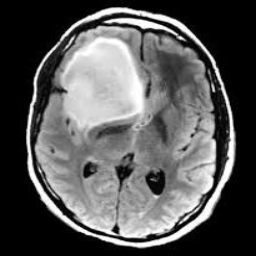

Figure 1: Heatmap Comparison of Unhealthy Images. Different columns show unhealthy MRI images of different positions, sizes, and textures. The first row is the raw image. The second row is the heatmap predicted with PatchCore. The third raw is the heatmap predicted with the proposed method.